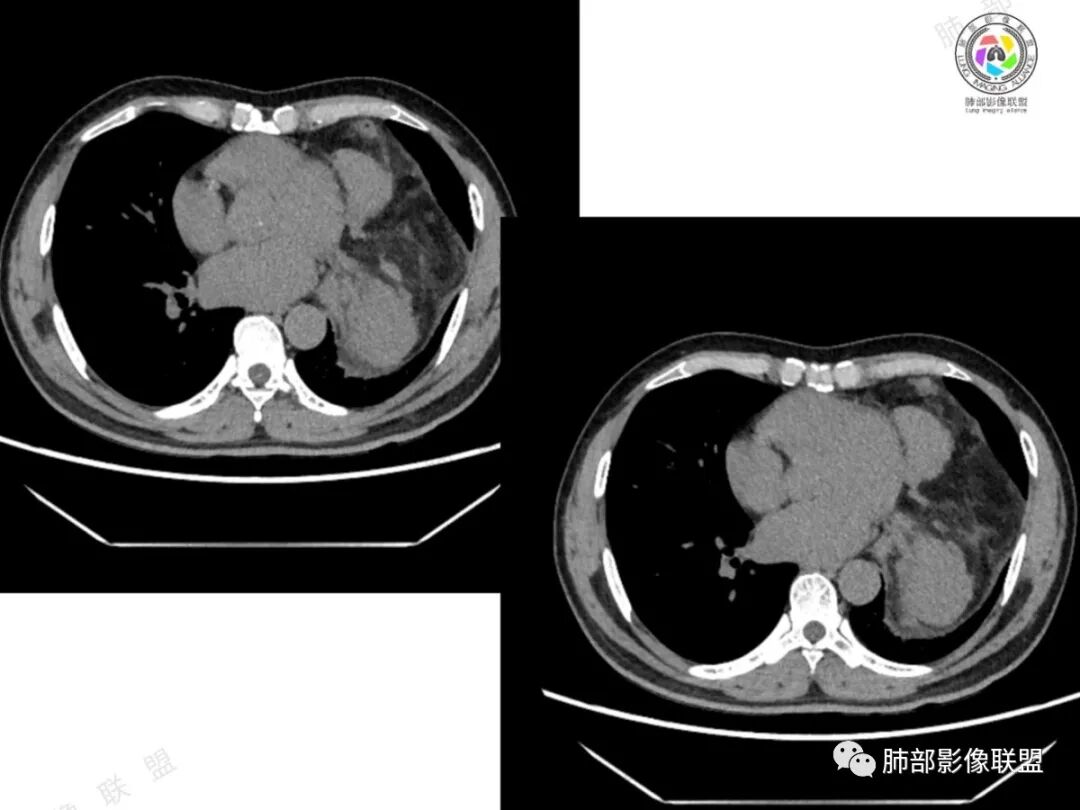

2、影像所见:左侧纵隔紧贴心包铸型生长巨大混杂密度肿块,边界清楚,临近结构受推挤移位,无明显外侵征象。肿块自主动脉弓旁一直顺延到至膈顶,呈“垂乳征”。病灶脂肪成分居多,斑片状、结节状及团块状实性密度成分散落其中,呈地图样分布,实性成分偶见低密度线样分隔,未见明确钙化影。增强扫描实性成分呈延迟明显强化,并见强化血管影。纵隔内有肿大淋巴结,未见胸腔积液,肺内及胸膜未见转移性病灶。

3、影像诊断:脂肪肉瘤?胸腺脂肪瘤?畸胎瘤?胸腺瘤?

①脂肪肉瘤:本例含较多脂肪组织,需考虑分化成熟型脂肪肉瘤(高分化型)的可能,其好发于前中纵隔的下部及心膈角区,肿块常大,偏于一侧,可有分叶,包膜可完整,与周围组织器官界限清楚。以脂肪密度为主的肿块,增强后仅见间隔或实性部分轻微强化。而本例实性成分过多,且实性病灶强化较明显,与高分化型脂肪肉瘤表现矛盾。

②胸腺脂肪瘤:好发于前下纵隔心膈角区,肿块一般较大,多见于40岁以下年龄患者,其内可见条状或片絮状胸腺组织,一般无周围侵犯。本例实性成分多、体积大,年龄较大,与胸腺脂肪瘤存在较多冲突。

③畸胎瘤:多见于年轻患者,除实体部分的软组织密度、液体部分的水样密度和脂肪组织的脂肪密度外,钙化和骨化较常见,特征性表现是可出现脂肪-液体平面,有时在此界面出现线状及条索状混杂密度影为毛发团。成熟囊性畸胎瘤由分化成熟的组织构成,可以只有脂肪和囊变或者只有囊变。本例年龄较大,未见明确钙化及骨化,畸胎瘤似乎缺乏影像学证据。

④胸腺瘤:常见于40岁以上患者,是最常见的前纵隔肿瘤,大多数位于前纵隔,其次为心包旁,常偏侧生长,多数密度均匀,大于15㎝罕见,一般轻-中度强化,少数可明显强化。黄勇老师认为,胸腺瘤病理标本上均伴有不同程度间隔存在,随着侵袭性增强,分隔会逐渐不显著。当病灶有明确分隔,较均匀强化时,胸腺瘤一定要考虑到。